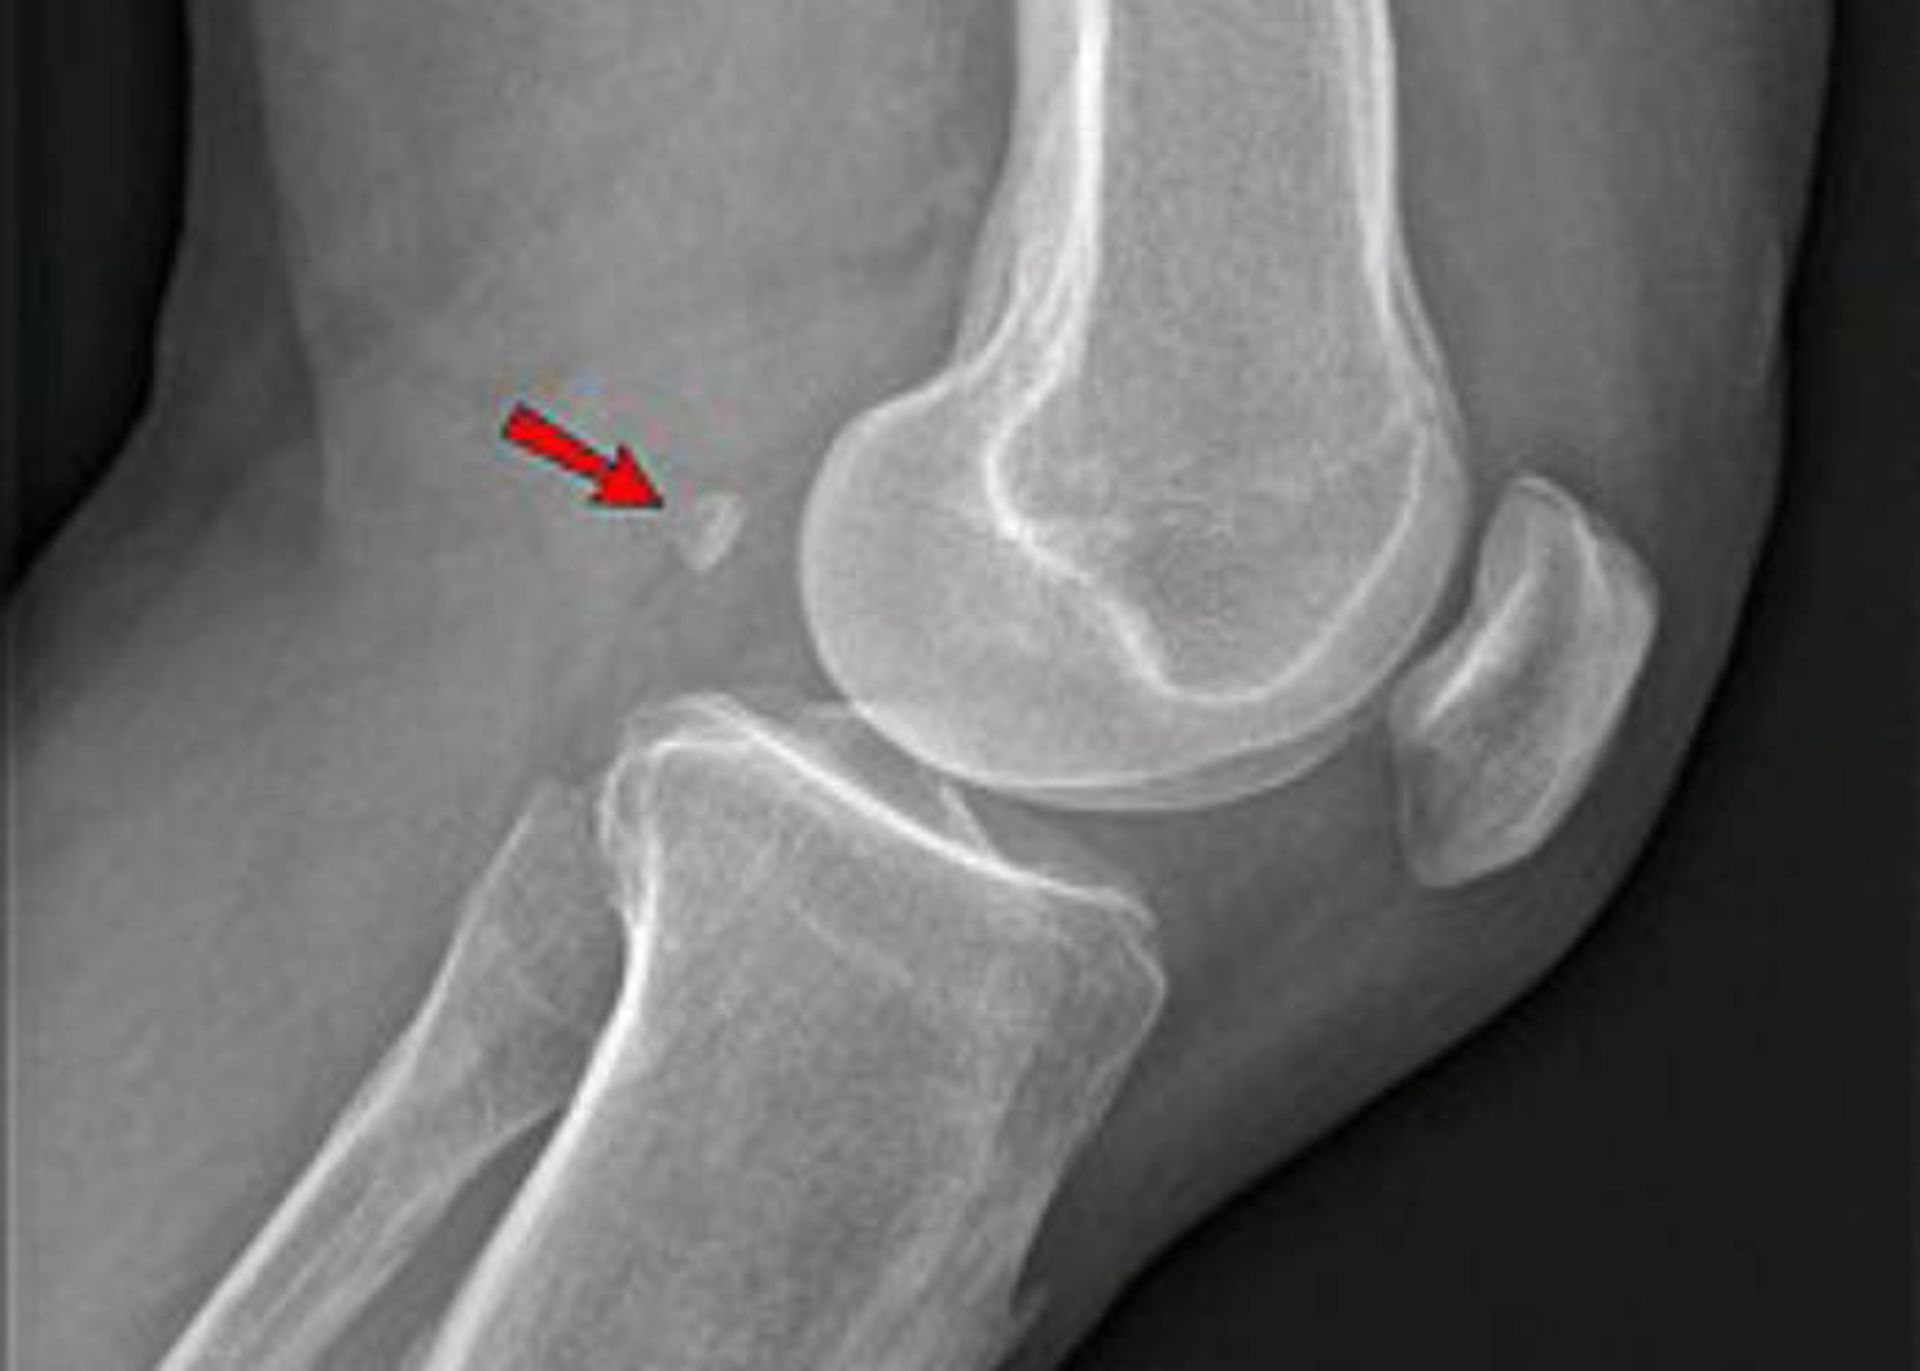

اخیرا دانشمندان بریتانیایی گزارش کرده‌اند استخوانی که قبلا تصور می‌شد در جریان تکامل در‌ حال ناپدیدشدن باشد، درحال‌بازگشت است. این استخوان کوچک که فابلا (لوبیای کوچک) نامیده می‌شود، اگر وجود داشته باشد، در پشت زانو قرار گرفته است. طبق برآورد دانشمندان، احتمال اینکه فردی در سال ۲۰۰۰ این استخوان را داشته باشد، تقریبا ۳.۵ برابرِ احتمال داشتن آن در سال ۱۹۰۰ است و البته، هدف دقیق حضور آن همچنان معما است.

استخوان فابلا